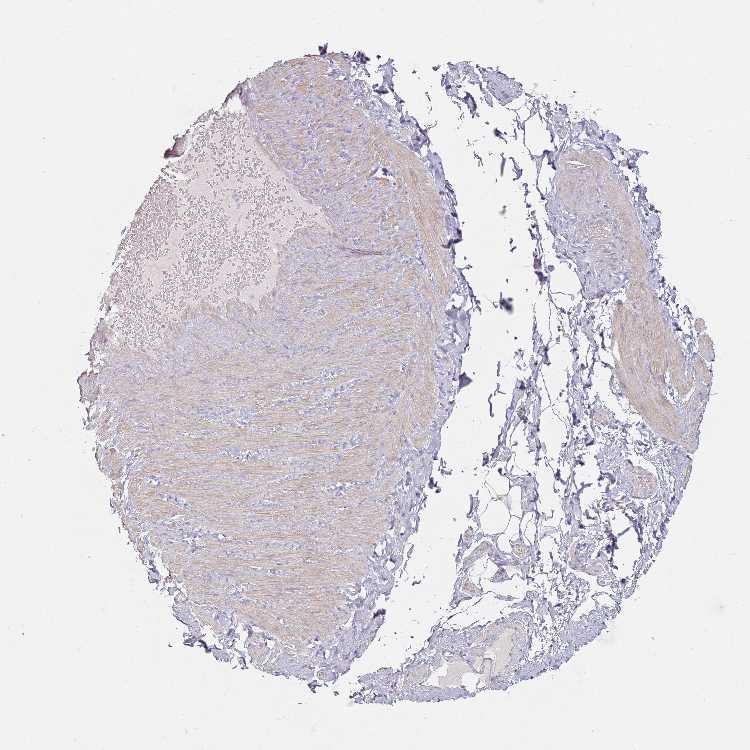

ADIPOSE TISSUE - Antibody stainingi

Antibody staining in the annotated cell types in the current human tissue is reported as not detected, low, medium, or high, based on conventional immunohistochemistry profiling in selected tissues. This score is based on the combination of the staining intensity and fraction of stained cells.

Each image is clickable and will lead to virtual microscopy that enables deeper exploration of all samples and also displays staining intensity scores, fraction scores and subcellular localization as well as patient and tissue information for each sample.

Antibody HPA045880Antibody HPA056474

Adipocytes Not detectedNot detected